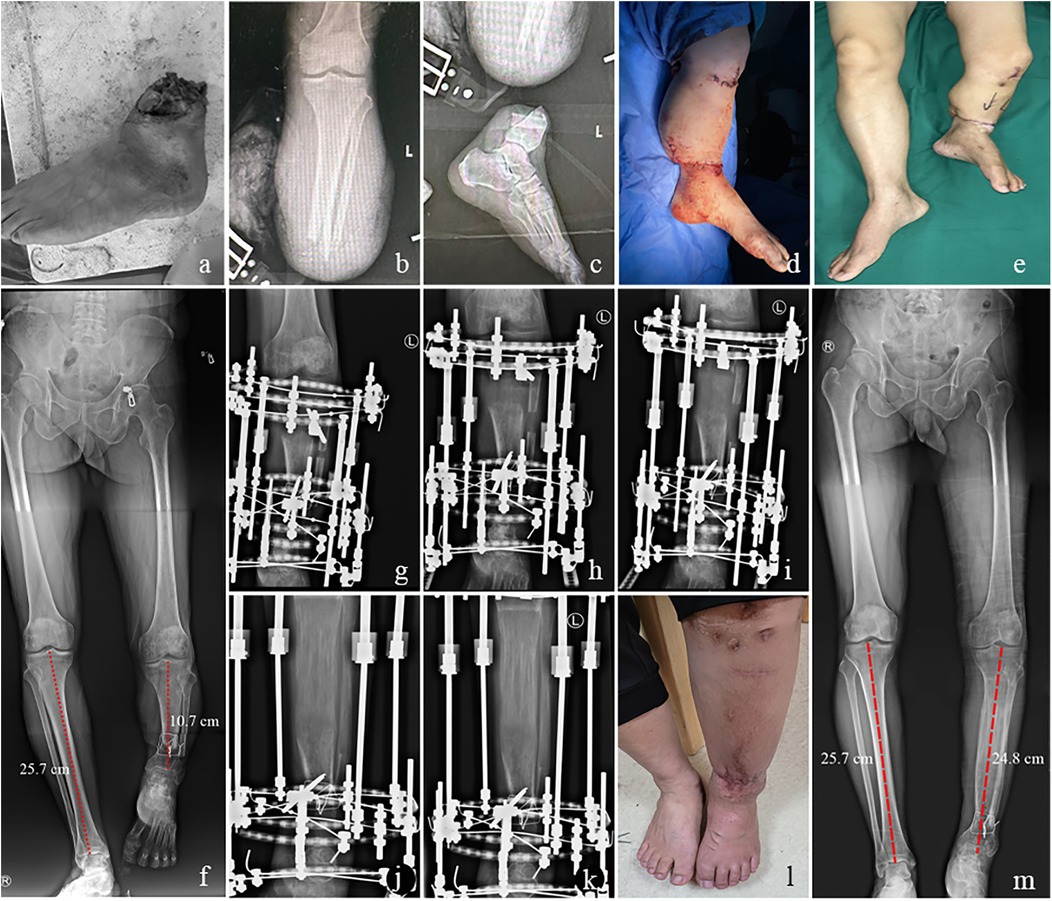

Figure 2

Series of medical images showing a foot with severe injury (a-c), post-surgical and healing stages (d-e), X-rays of legs with measurements (f, m) and external fixators (g-k), and healed leg (l).

Figure 2. A 51-year-old male with limb shortening deformity after replantation of lower leg amputation treated by limb lengthening using an external fixator. (a) Traumatic amputation of the distal left lower leg. (b,c) x-rays of left tibia. (d) Replantation of the affected limb after shortening approximately 15 cm. (e) Successful limb salvage. (f) The full-length x-ray of the lower limb showed a shortening of about 10 cm in the left lower leg. (g) Postoperative x-ray of the left tibia. (h–j) x-ray of the left tibia at one month, 3 months and 5 months after surgery. (k,l) The consolidation phase was completed with satisfactory bone union and limb function recovery at the 21 postoperative month. (m) The full-length x-ray of the lower limb revealed a shortening of approximately 0.9 cm in the left lower leg, which is generally considered acceptable.